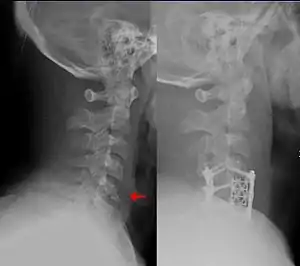

Orthopedic surgery or orthopedics (alternatively spelt orthopaedics), is the branch of surgery concerned with conditions involving the musculoskeletal system.[1] Orthopedic surgeons use both surgical and nonsurgical means to treat musculoskeletal trauma, spine diseases, sports injuries, degenerative diseases, infections, tumors, and congenital disorders.

![]() This fracture of the lower cervical vertebrae is one of the conditions treated by orthopedic surgeons and neurosurgeons. | |